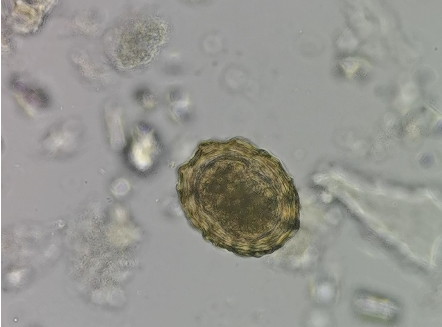

在食品安全检测中,微生物污染及寄生虫卵检测多是通过显微镜明场观察方式,食品中的微生物种类繁多,颗粒小且数量不等,对显微成像的分辨率要求较高。而寄生虫卵尺寸小且常常与食品中其他成分混杂,要求显微镜能够清晰区分细微的结构差异,特别是在一些肉类样本中,需要具有较高的对比度和图像清晰度。最后是非法添加物筛查,低浓度样本通常依赖荧光显微镜技术,这要求显微镜具备出色的荧光成像能力,能够精准识别和定位微小的染料颗粒。

生物显微镜下观察和拍摄的蛔虫卵